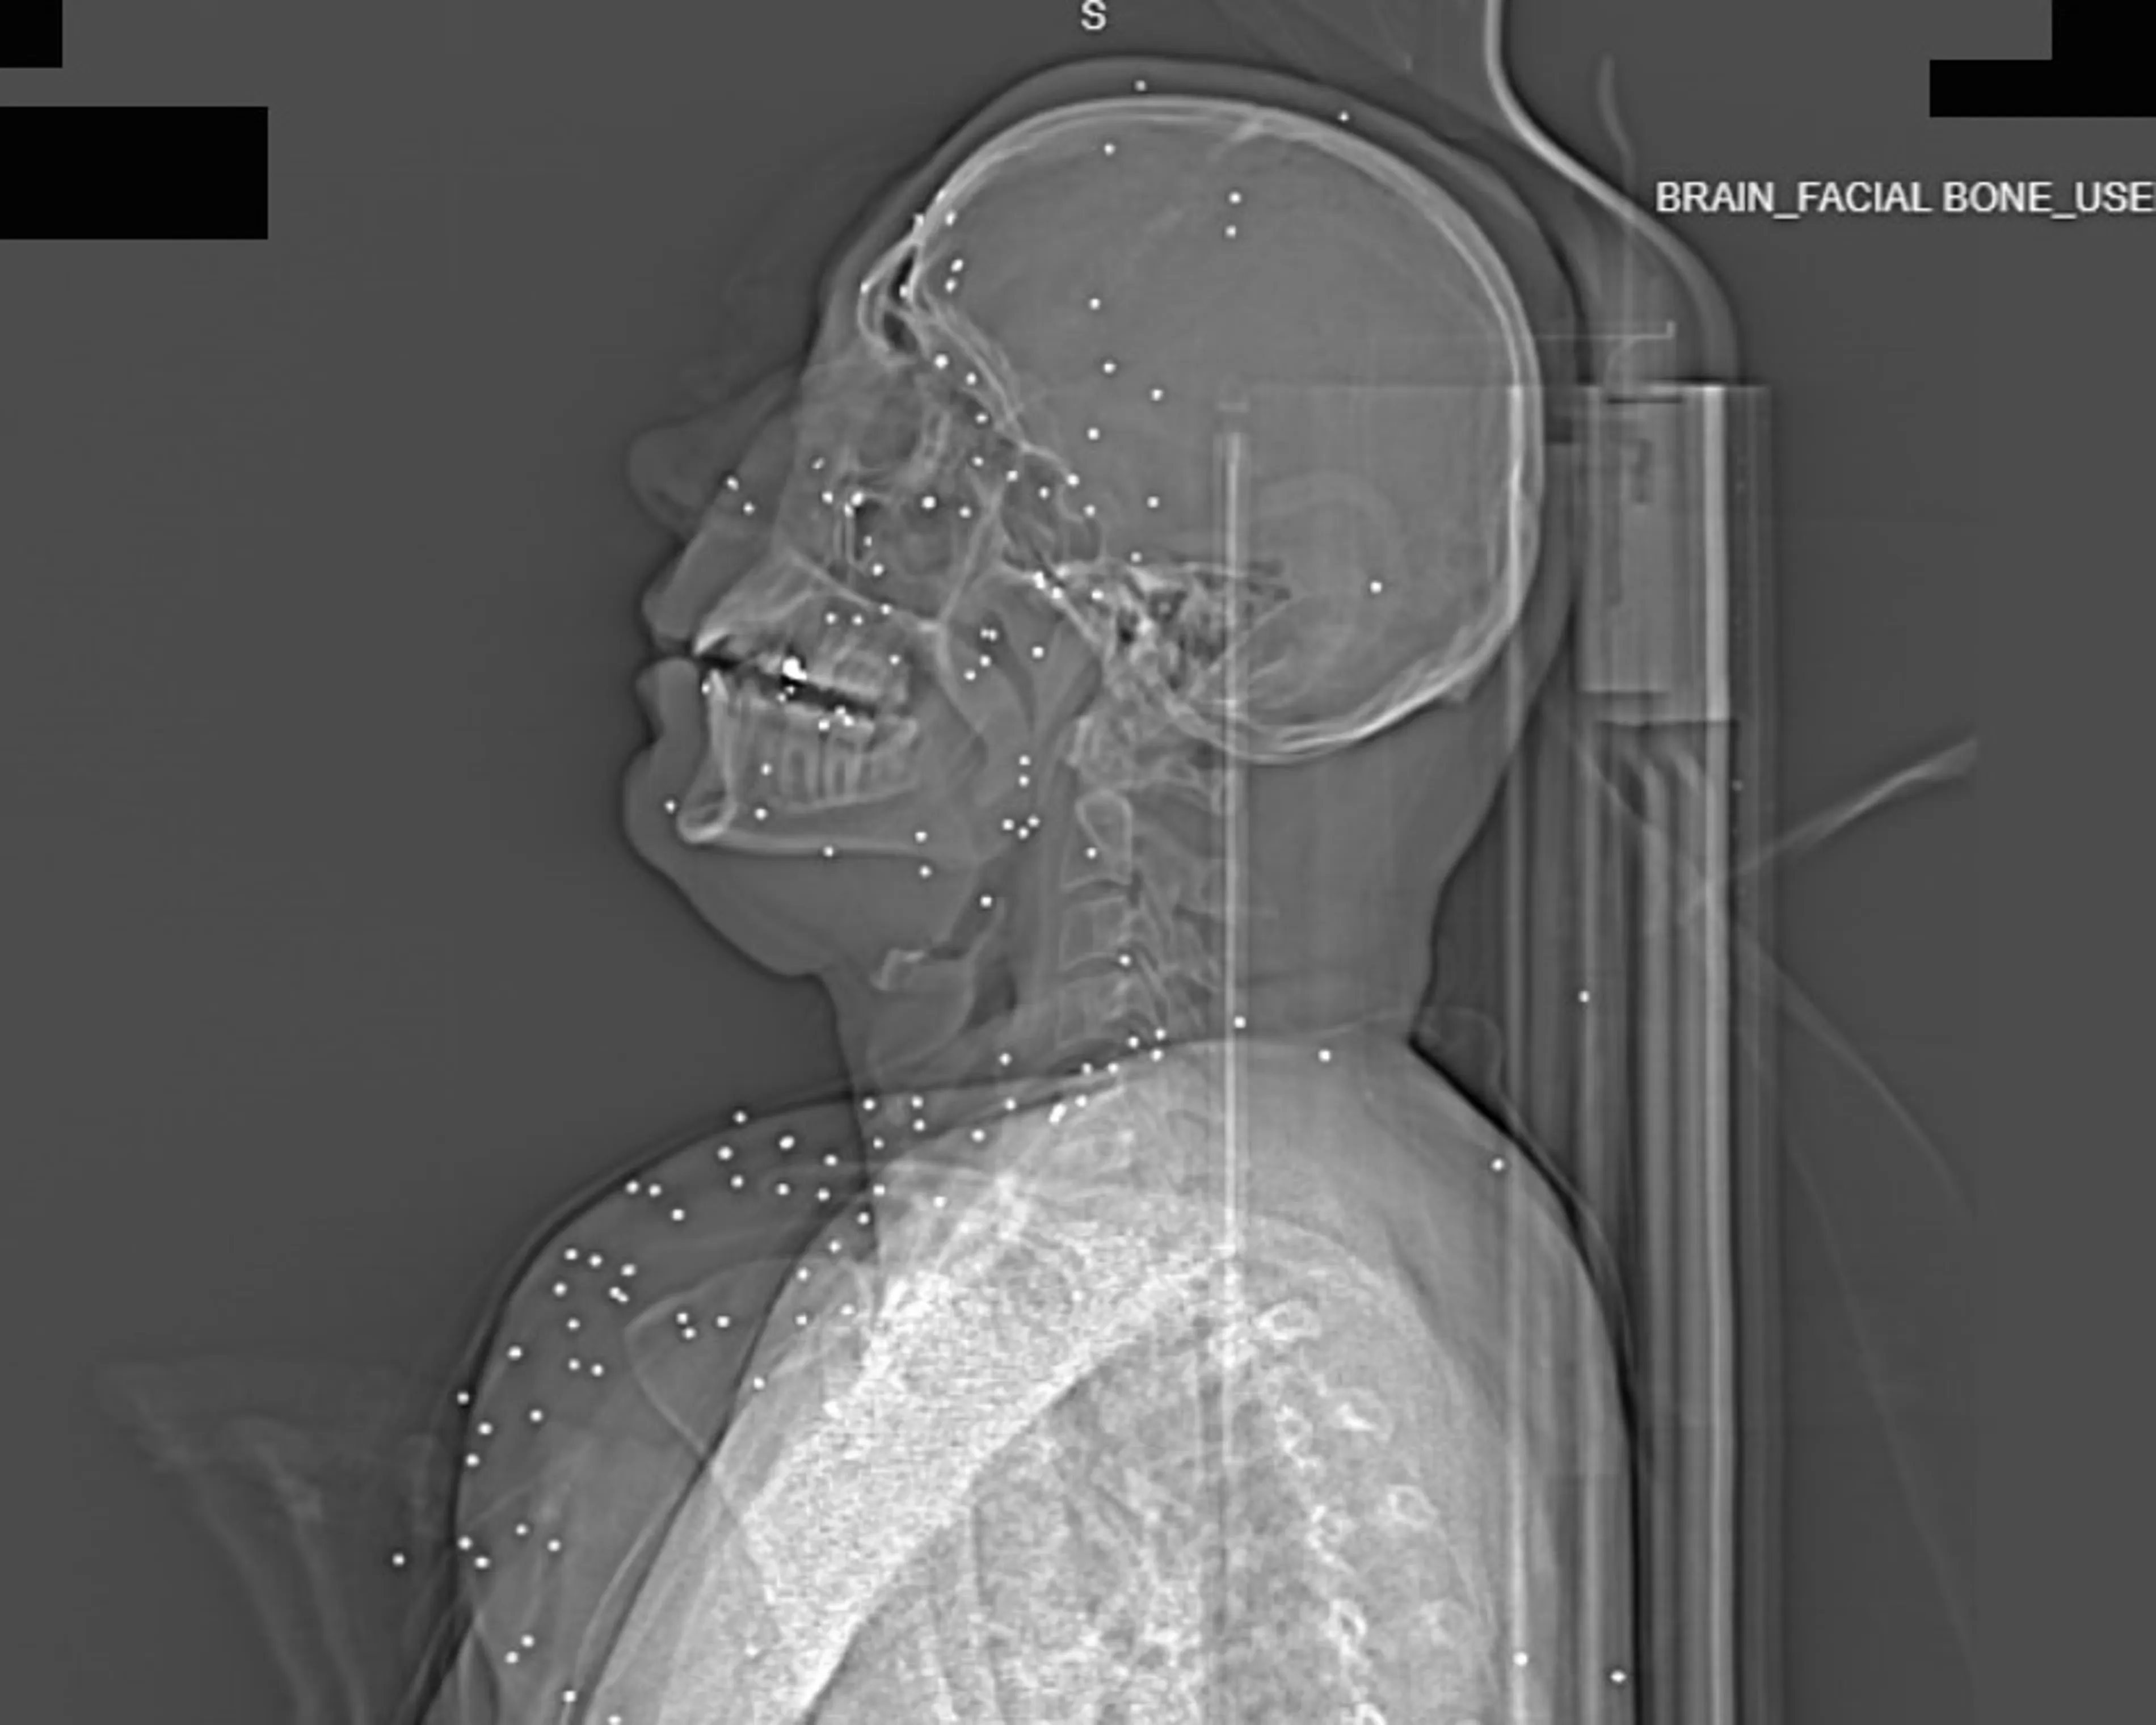

Деякі пацієнти отримували прямі кулі у голову. Один чоловік має кулю в мозку з газовою бульбашкою – травма вважається смертельною. Інший – із кулями біля хребта. Медичні експерти підтверджують, що це зброя, призначена для вбивства, а не для стримування натовпу. В окремих випадках постраждалі отримували поранення в геніталії та тазову область. Одна жінка середнього віку була поранена дробом у стегна та таз – майже 200 металевих куль залишилися всередині її тіла. Лікарі попереджають, що такі травми часто призводять до інвалідності, стерильності та уражень сечовидільної системи.

Фахівці також підкреслюють закономірність у пораненнях: більшість людей стріляли в обличчя, груди та геніталії. Це свідчить про цілеспрямоване завдання шкоди, а не випадкові постріли. «Це не випадкове влучання в хаотичному натовпі, це націлене поранення життєво важливих частин тіла», – зазначає один із лікарів. Серед постраждалих були і діти, і люди похилого віку. Один із медиків розповів про 14-річну дівчинку, якій вистрілили прямо в ліве око. Травма була настільки тяжкою, що око довелося видалити. Її молодший брат та батьки були в шоці – хлопчик тремтів, а мама намагалася врятувати дитину під час хаосу на протестах.